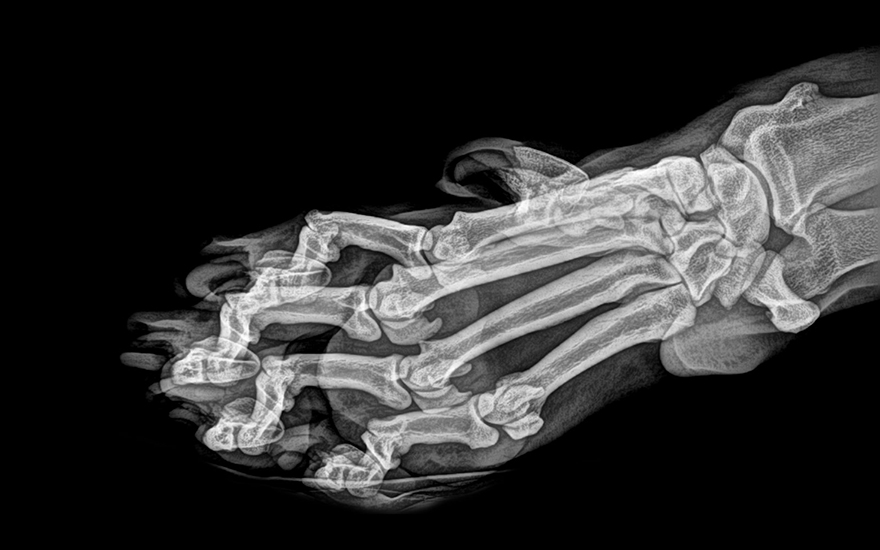

#3

Image Source - Twitter ; Image Courtesy - Oregon Zoo

ஒரிகன் விலங்கியல் பூங்காவின் புலியின் கால்கள்-ன் எக்ஸ்ரே புகைப்படம்.